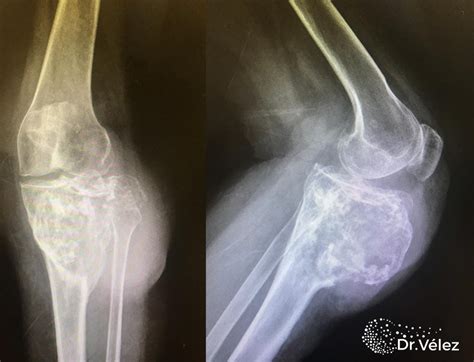

La paleopatología, el estudio de las enfermedades en restos antiguos, ha proporcionado información valiosa sobre las afecciones de la piel que afectaban a las poblaciones del pasado. Los análisis de huesos y tejidos blandos preservados han revelado evidencia de tumores, infecciones y otras enfermedades cutáneas.

Por ejemplo, se han encontrado casos de osteosarcoma en homínidos de hace 1.7 millones de años, así como tumores osteogénicos en Australopithecus sediba. También se han documentado casos de cáncer metastásico de próstata en momias egipcias ptolemaicas y teratomas mediastinales de hace 1800 años.

Estos hallazgos demuestran que el cáncer, una enfermedad que a menudo asociamos con la vida moderna, ha existido durante milenios y ha afectado a nuestros antepasados de diversas formas.